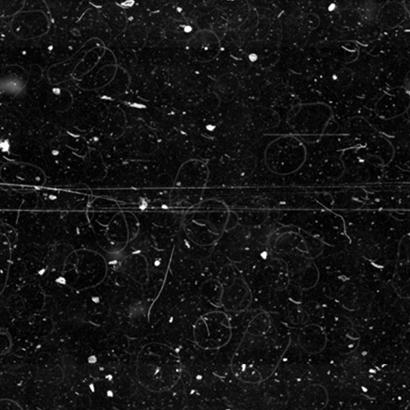

Irregular and Rippled SurfaceShows height variations that compromise image consistency and quality. |

Risk of Inefficient WorkflowsCan lead to suboptimal scans, reducing lab efficiency and requiring time-consuming rescans. |